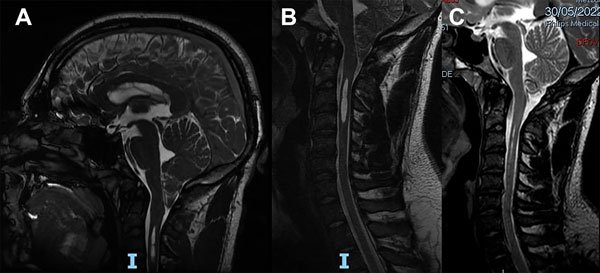

Un varón de 22 años de edad, deportista de contacto profesional, consultó por presentar una MCI con SM. Sólo presentaba apneas de sueño confirmadas por una polisomnografía. La RM mostraba un descenso amigdalino de 17 mm y una SM ubicada entre C3 y C4 (Figura 7A-B). Teniendo en cuenta su profesión y los síntomas se indicó cirugía. Se le realizó una descompresión cráneo cervical y duraplastia con periostio. La evolución postoperatoria transcurrió sin complicaciones. A los 5 meses de la cirugía se le realizó una RM en contraste de fase en donde se observó que la SM no se había reducido y las velocidades del LCR eran de 10 cm/seg. Siguió bajo control y a los 16 meses de la cirugía se observó la desaparición de la SM (Figura 7C) y en la nueva RM en contraste de fase la normalización de las velocidades del LCR (2,3 cm/seg.). Fue dado de alta definitivamente pudiendo reasumir su actividad deportiva.

Figura 7: Caso 5. A: RM de cerebro en plano sagital ponderada en T2 que muestra el descenso amigdalino de 17 mm de configuración de bordes agudos y el extremo proximal de una siringomielia cervical. B: RM de columna cervical en plano sagital ponderada en T2 que muestra una siringomielia entre C3 y C4. C: RM de columna cervical en plano sagital ponderada en T2 que muestra la resolución de la siringomielia.